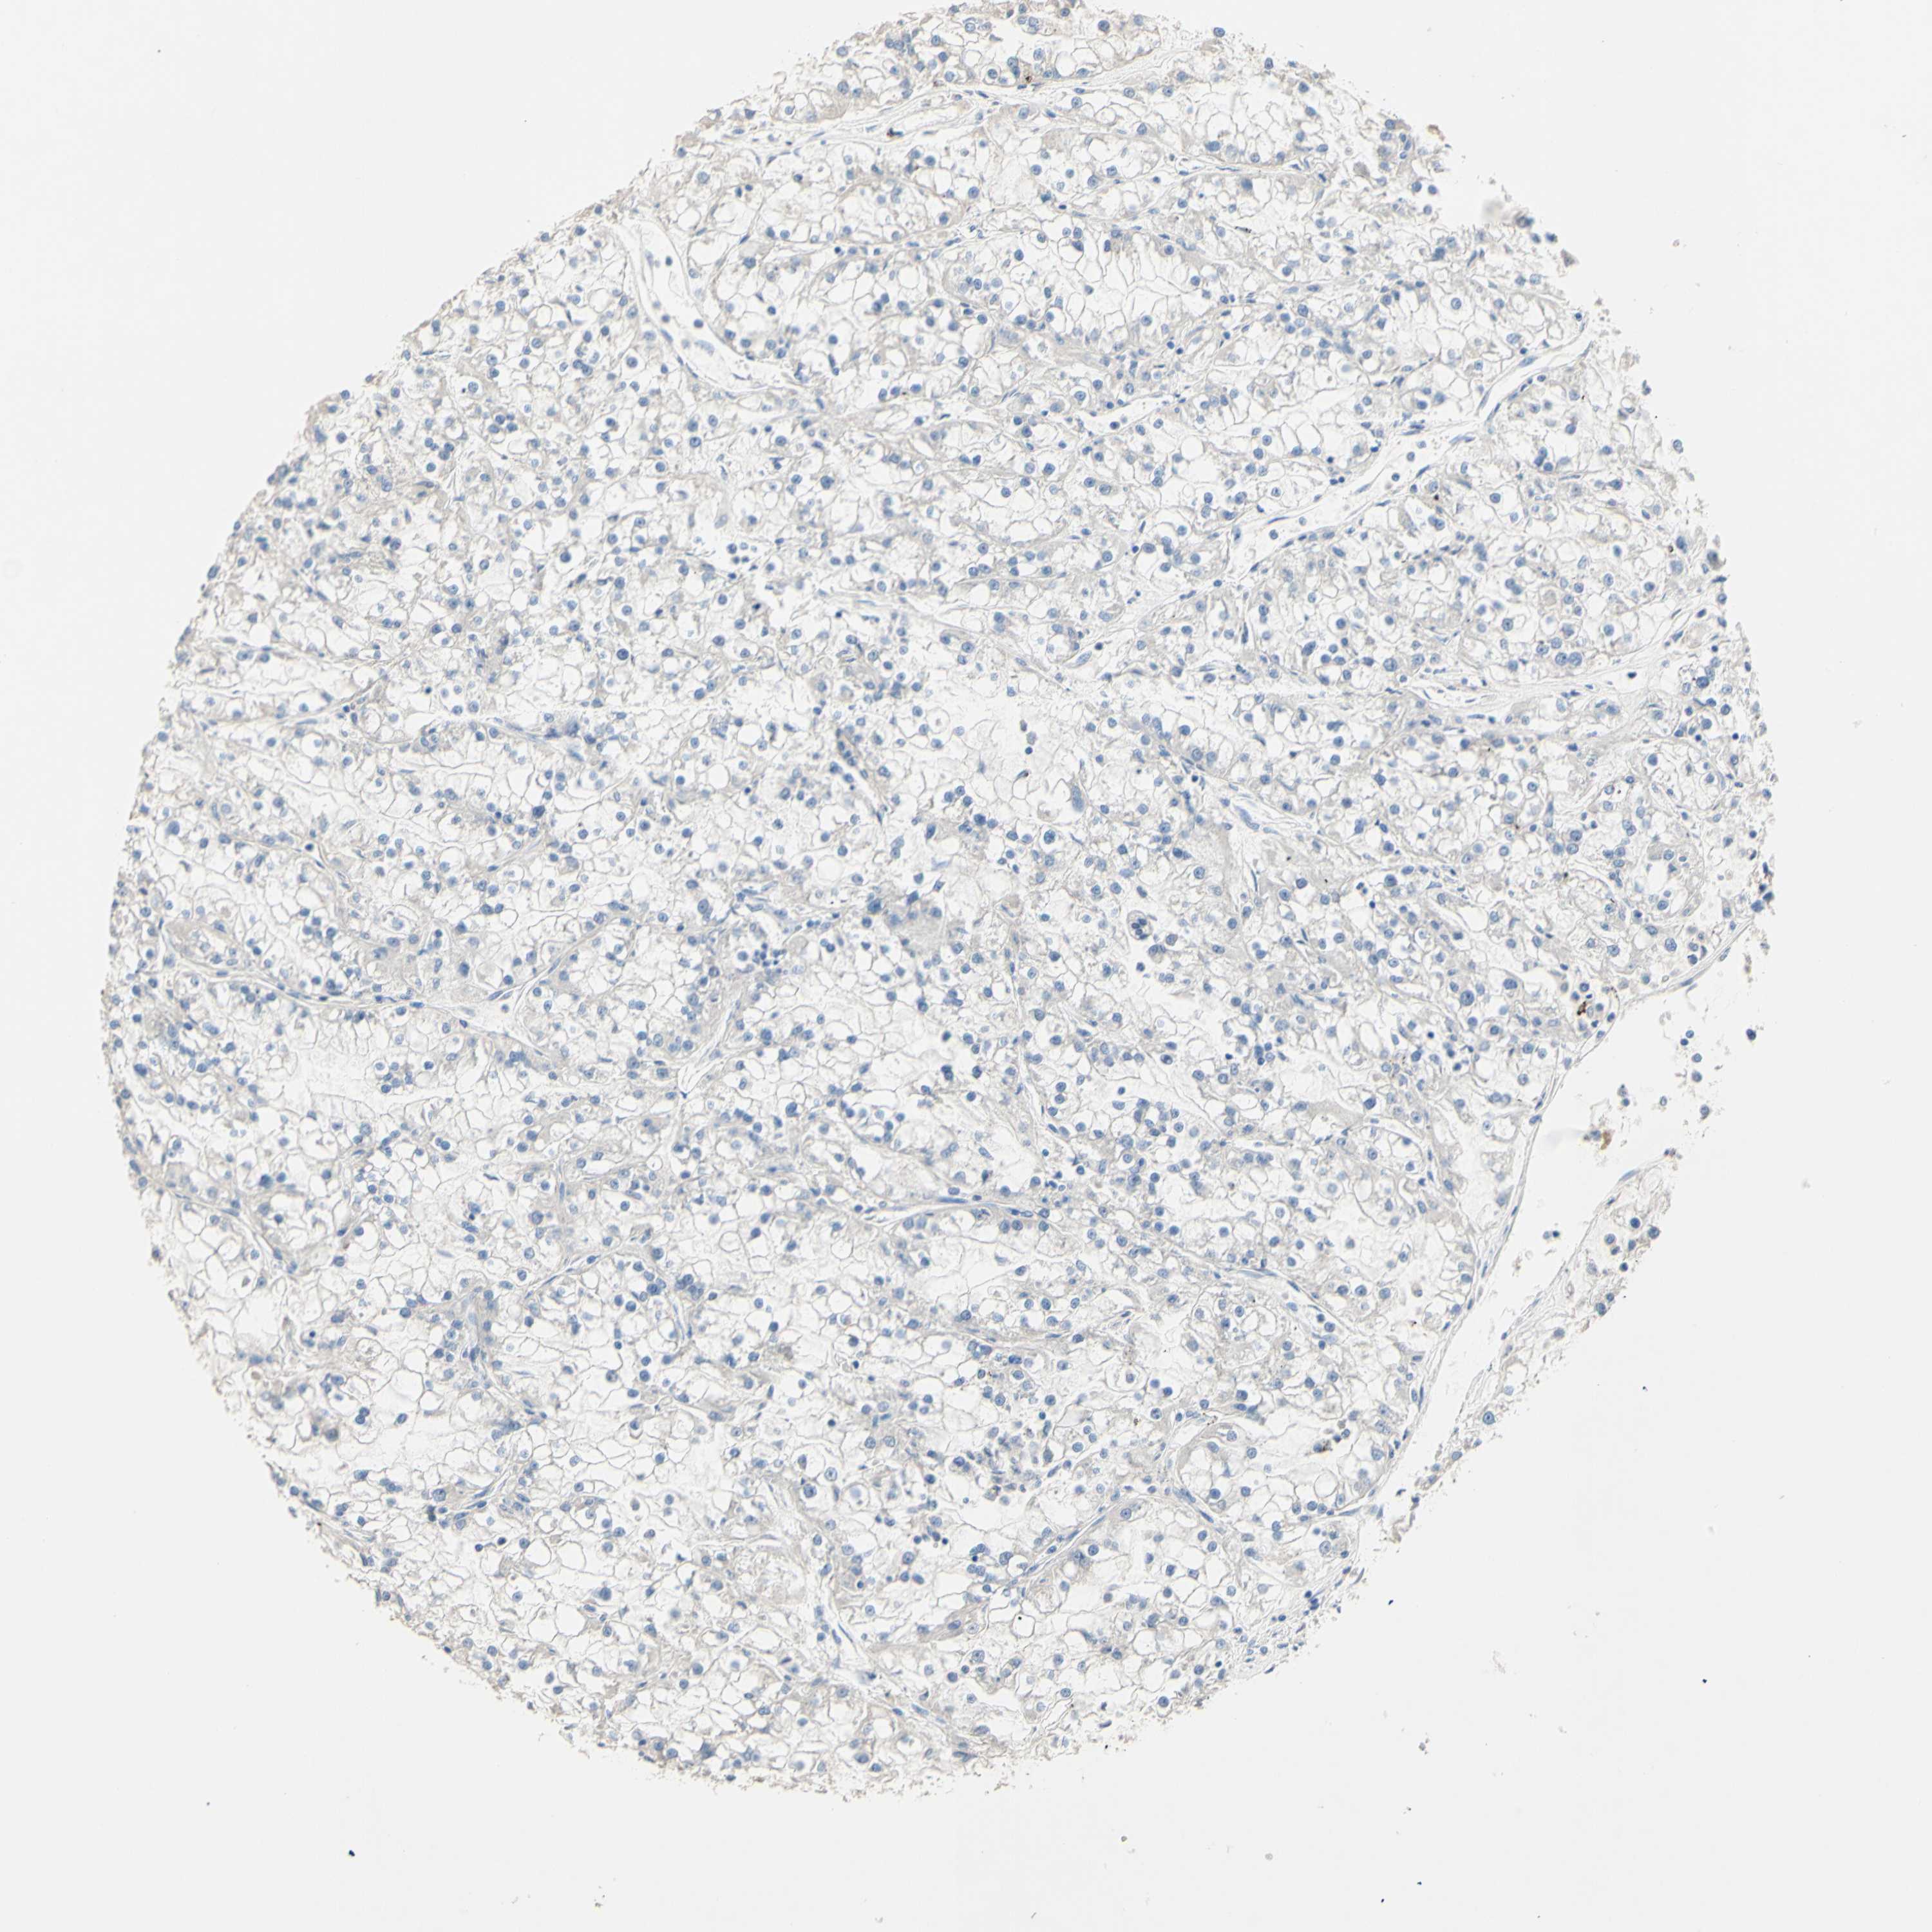

CANCER RENAL CANCER Show tissue menu

Renal cancer

Kidney chromophobe

KIDNEY CHROMOPHOBE (TCGA) - Interactive survival scatter ploti

The Survival Scatter plot shows the clinical status (i.e. dead or alive) for all individuals in the patient cohort, based on the same data that underlies the corresponding Kaplan-Meier plots. Patients that are alive at last time for follow-up are shown in blue and patients who have died during the study are shown in red.

The x-axis shows the expression levels (FPKM) of the investigated gene in the tumor tissue at the time of diagnosis. The y-axis shows the follow-up time after diagnosis (years). Both axes are complimented with kernel density curves demonstrating the data density over the axes. The top density plot shows the expression levels (FPKM) distribution among dead (red) and alive patients (blue). The right density plot shows the data density of the survived years of dead patients with high and low expression levels respectively, stratified using the cutoff indicated by the vertical dashed line through the Survival Scatter plot. This cutoff is automatically defined based on the FPKM cutoff that minimizes the p-score. The cutoff can be changed by dragging the vertical line or by entering a cutoff value in the square labeled "Current cut-off".

Under the Survival Scatter plot the p-score landscape (black curve; left axis) is shown together with dead median separation (red curve; right axis). Dead median separation is the difference in median mRNA expression between patients who have died with high and low expression, respectively. It is calculated as follows: median FPKM expression of dead patients with high expression - median FPKM expression of dead patients with low expression. This is intended to aid the user in visually exploring custom cutoffs and the associated p-scores and dead median separation.

Individual patient data is displayed and can be filtered by clicking on one or more of the category buttons on the top of the page. Categories describing expression level and patient information include: high, low, alive, dead, female, male and tumor stages. The scale of the x-axis can be toggled between linear and log-scale by clicking on the "x log" button. Mouse-over function shows TCGA ID, patient information and mRNA expression (FPKM) for each patient.

& Survival analysisi

Kaplan-Meier plots summarize results from analysis of correlation between mRNA expression level and patient survival. Patients were divided based on level of expression into one of the two groups "low" (under cut off) or "high" (over cut off). X-axis shows time for survival (years) and y-axis shows the probability of survival, where 1.0 corresponds to 100 percent.

CDON is not prognostic in Kidney Chromophobe (TCGA)